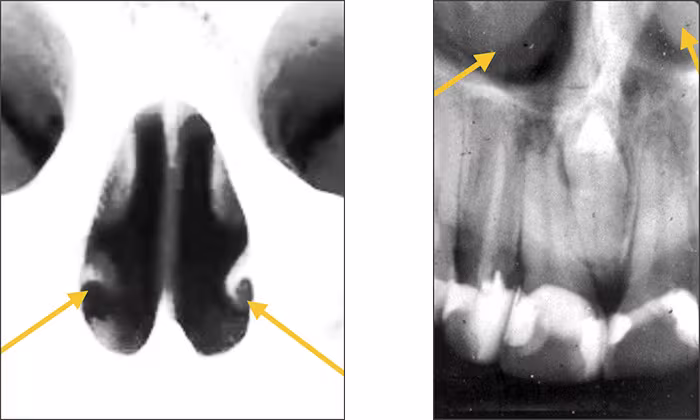

Inverted Y – The inverted Y is a radiographic landmark that depicts where the nasal fossa crosses the maxillary sinus. The boundary between them is shaped like an upside-down letter Y, hence its name. The periapical images below demonstrate the inverted Y, a classic radiographic landmark of the right and left anterior maxilla. The fossa is positioned toward the midline while the sinus extends toward the posterior aspect of the maxilla. Typically, the inverted Y sits apical to the maxillary lateral incisor and canine teeth. No comparable structures are found in the mandibular lateral incisor and canine areas which differentiates maxillary from mandibular anterior periapical images.

Nasal soft tissue – The soft tissue of the nose, including the tip and ala (corner of the nose), often can be seen superimposed over the roots of the teeth on anterior periapical images. The nasal soft tissue appears radiopaque.